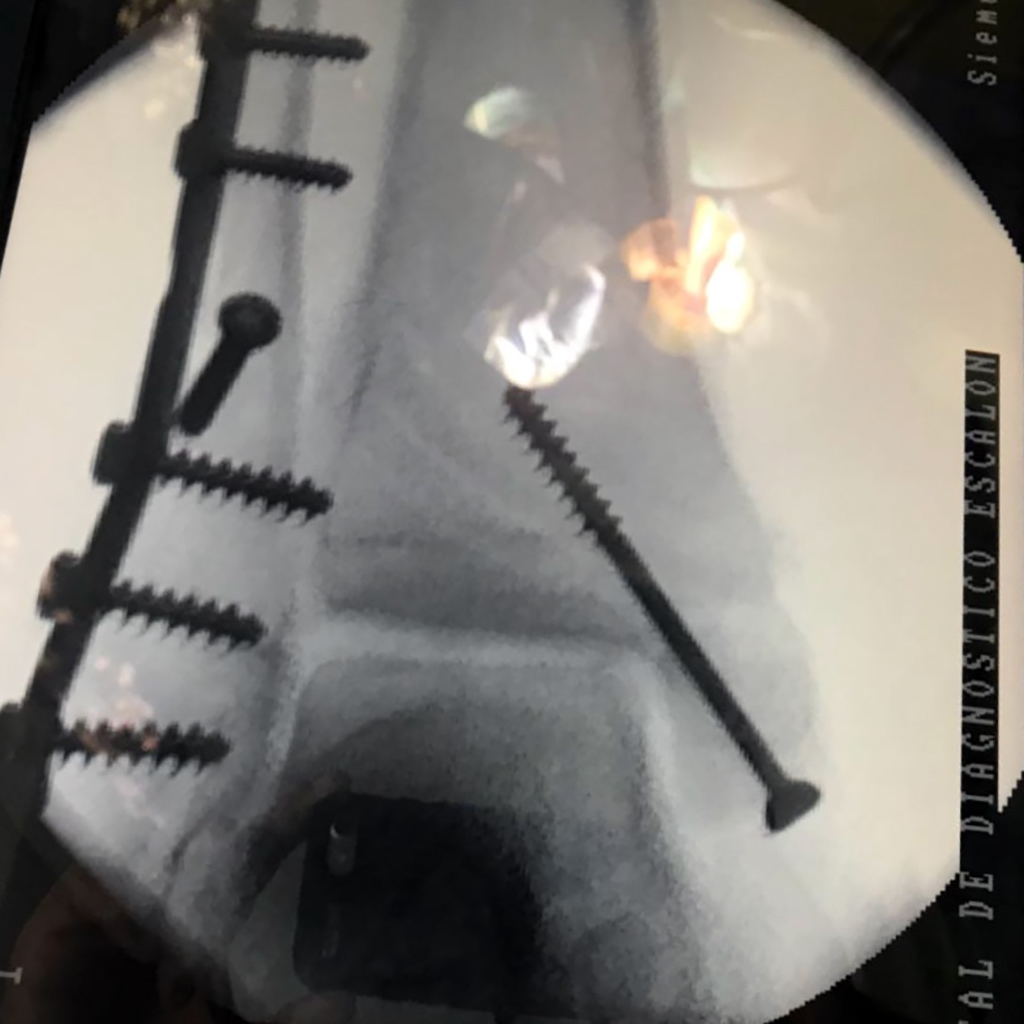

Cuando se necesita cirugía, es probable que esta implique el uso de clavijas de metal, tornillos o placas para sostener los huesos en su lugar mientras la fractura se consolida. Los elementos de soporte pueden ser temporales o permanentes.